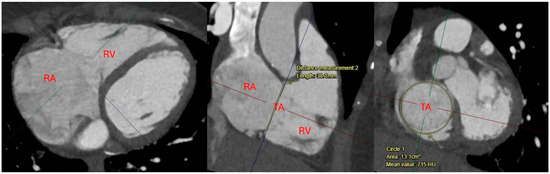

| Computed Tomography (CT) | Primarily used for anatomical assessment of the tricuspid valve and surrounding structures. Useful in pre-procedural planning for transcatheter interventions, identifying lead-associated complications, and assessing right atrial and ventricular size [21,23]. | High spatial resolution for anatomical evaluation of the tricuspid valve, right heart chambers, and adjacent structures. Useful for identifying lead placement issues, fibrosis, and pre-procedural planning for transcatheter valve interventions [21,23]. | Exposure to ionizing radiation and contrast agents. Limited ability to assess hemodynamics in real-time. Not ideal for repeated follow-up imaging due to cumulative radiation exposure [21,23]. |